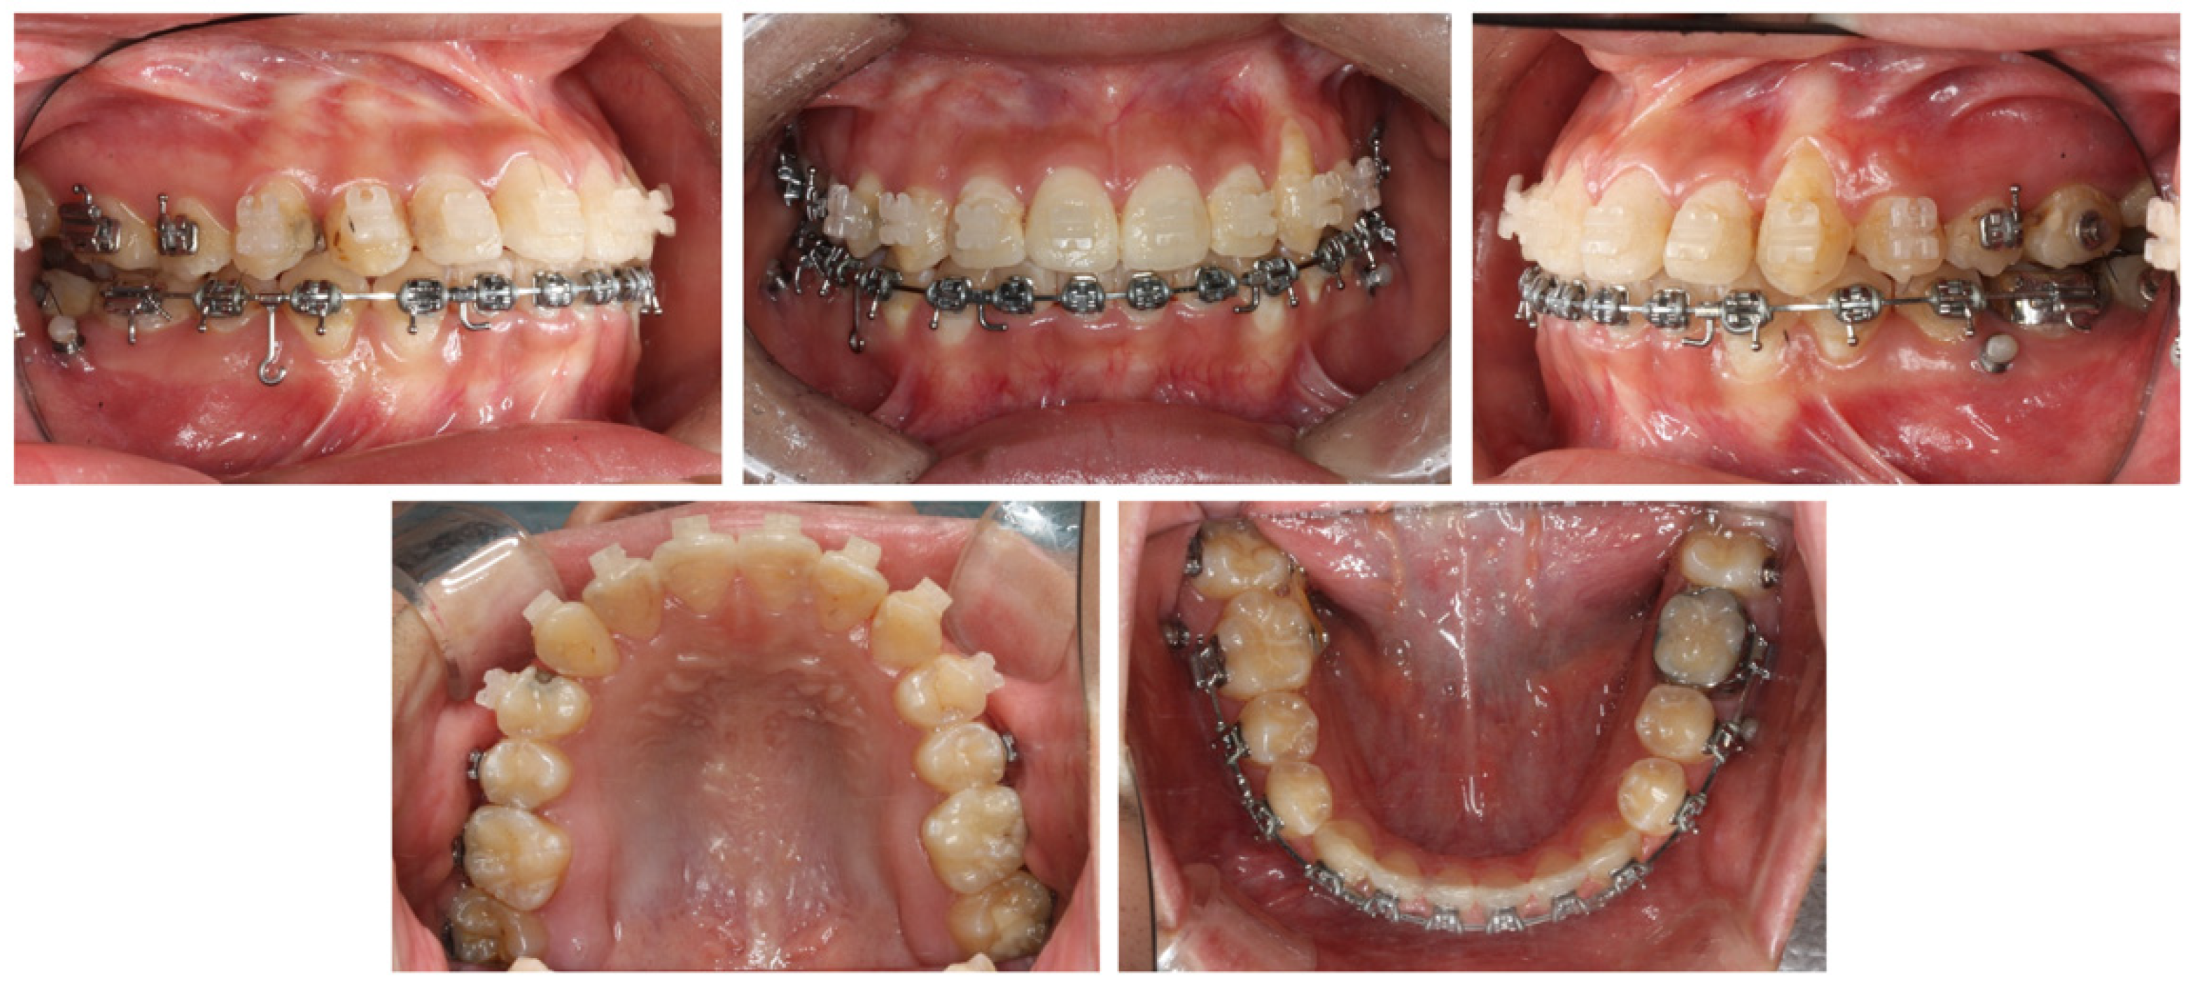

2.4. Treatment Progress

2.5. Treatment Results